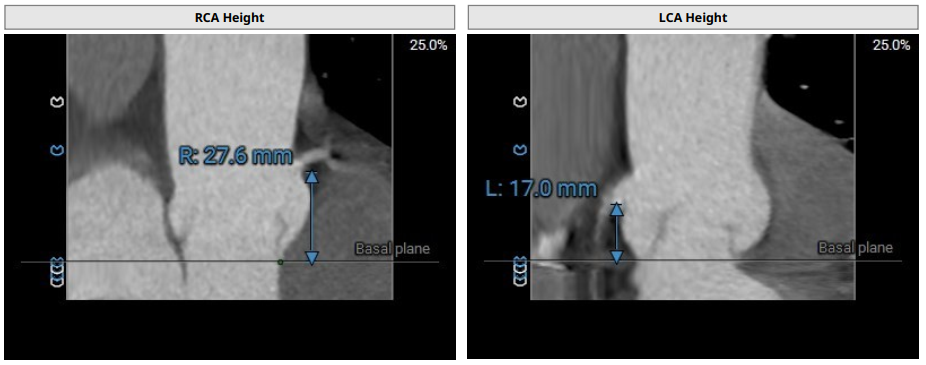

术前评估

术前影像评估提示,患者为典型三叶瓣结构,瓣窦分布均匀,无明显钙化,主动脉瓣环直径29.3mm,左室流出道直径30.6mm,STJ直径37.8mm,升主动脉直径40.5mm,双侧冠脉开口高度充足(左冠17.0mm,右冠27.6mm),无冠脉阻塞风险,左室-主动脉夹角137°,存在一定同轴性挑战。

CTA评估(上下滑动查看更多照片)

瓣膜选型:JS/TAVI-31瓣膜